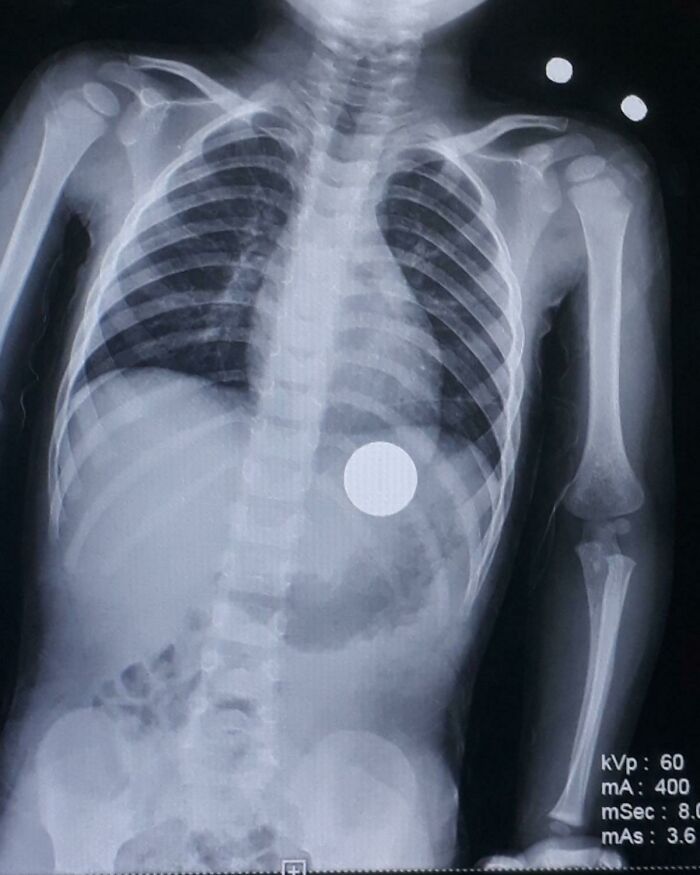

Dude who compulsively ate coins had about 7 bucks of change inside when opened up. He died choking on a quarter. Honestly, I like to think he died doing what he loved. Bonus: his younger brother also swallowed coins but the mystery is one penny went missing. Where did it go? The mystery lives on.